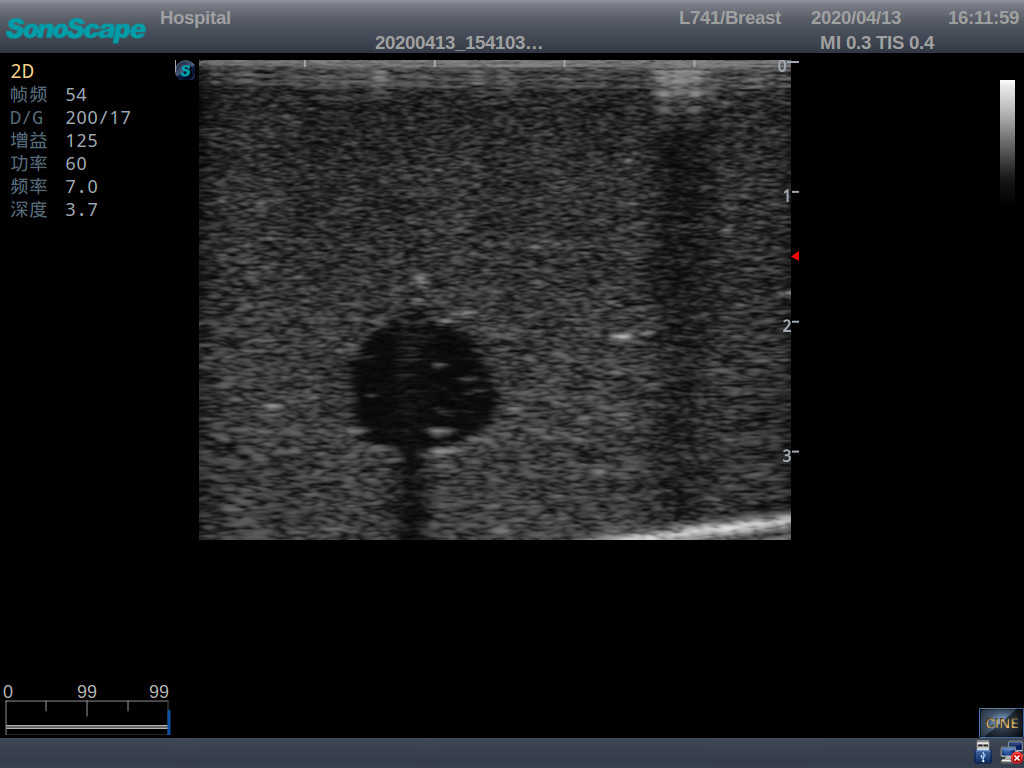

Outline

4) Biomimetic material allowing users to see clear and real normal tissues and space-occupying lesions that are hyperechoic, hypoechoic and isoechoic as they would see in the clinical environment